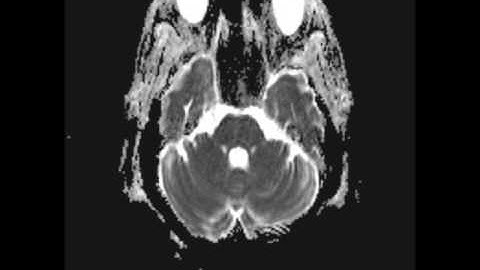

Trigeminal neuralgia due to vascular compression (Radiopaedia.org) Cases in Radiology